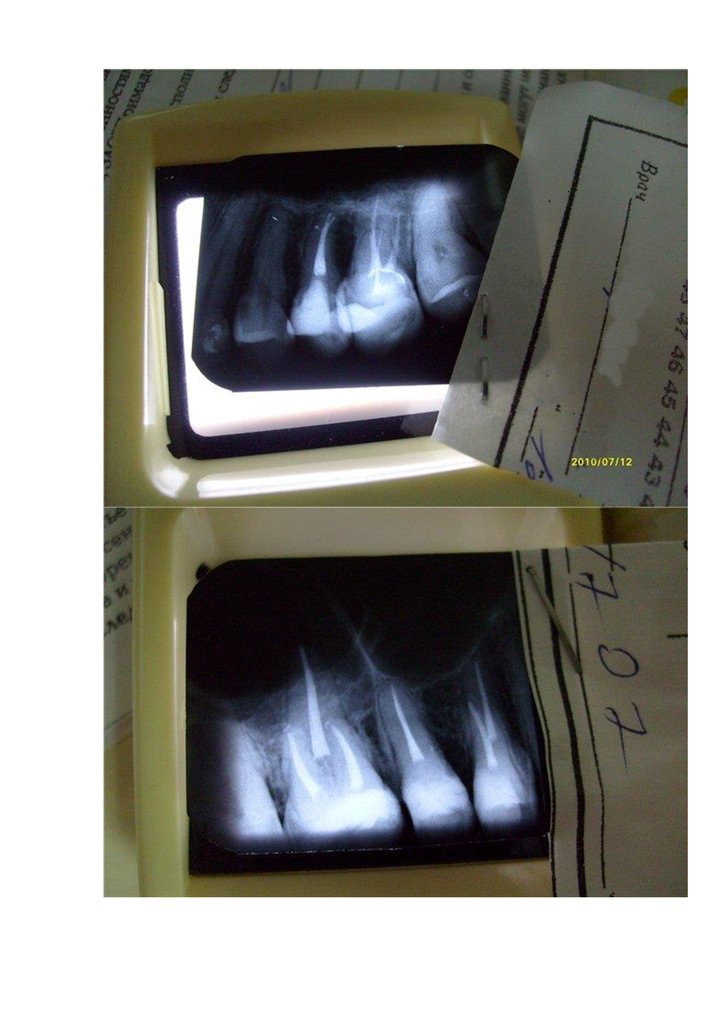

затрамбовываем ватой аккуратно и идем на калибровочный снимок.

Если во время обработки файлами апикальной части из какого-нибудь канала пошла

кровь- есть основания предполагать о перфорации апекса из-за вранья апекслокатора,

или не удается до апекса пройти- то снимок делается на этом этапе, а после

корректировки упора и прохождения ступени еще раз повторяем рентген.

Со всем справились, рентген подтвердил- значит канал СФОРМИРОВАЛИ.